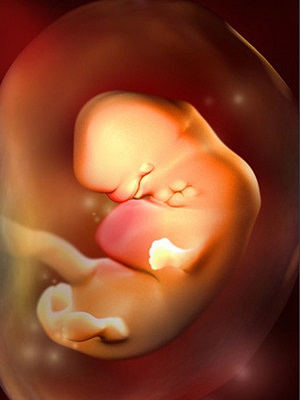

胚胎图

胚芽正在你的子宫深处迅速生长。这时候,宝宝的胚胎长度约0.4-0.5厘米,有一个小苹果籽大小,但是看起来还不像人,更像一只小蝌蚪。宝宝的心脏开始有规律的跳动及开始供血。

本周细胞迅速分裂,主要的器官如肾脏和肝脏开始生长。连接脑和脊髓的神经管也开始工作,原肠开始发育。胚胎的上面和下面开始形成肢体的幼芽,将来形成宝宝的手和腿。将来形成嘴巴的地方的下方有些小的皱摺,它将来会发育成宝宝的脖子和下巴。本周面部器官开始形成,鼻孔可清楚地看到,眼睛的视网膜也开始形成了。